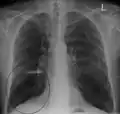

Chest X-ray demonstrating severe COPD, displaying small heart size in comparison to the lungs A lateral chest X-ray of a person with emphysema, displaying barrel chest and flat diaphragm

A lateral chest X-ray of a person with emphysema, displaying barrel chest and flat diaphragm Lung bulla as seen on chest X-ray in a person with severe COPD

Lung bulla as seen on chest X-ray in a person with severe COPD A severe case of bullous emphysema